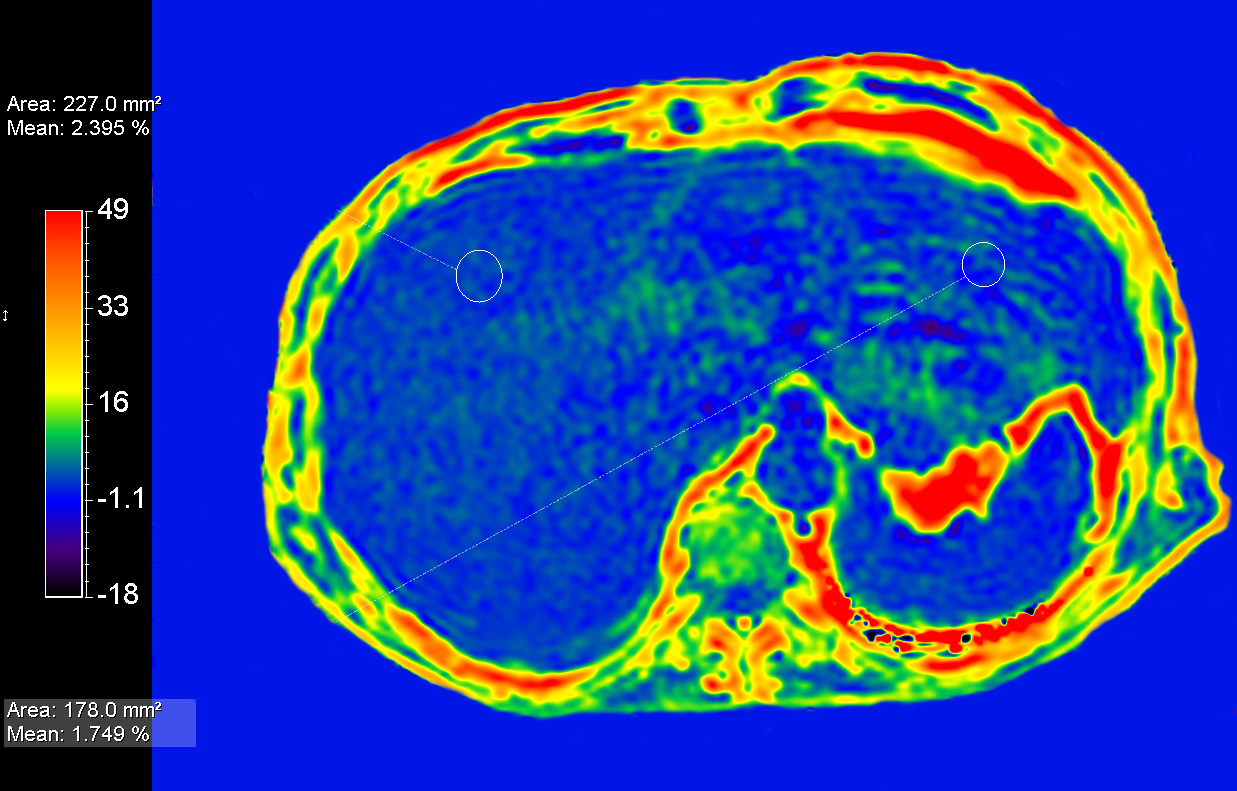

Patient with liver metastasis. The ExamCard includes techniques for efficient fat-free imaging over large field-of-views (mDIXON XD), a procedure for non-invasive liver fat quantification (mDIXON Quant), a multi-phase contrast-enhanced sequence (4D FreeBreathing) to improve imaging confidence and Compressed SENSE to accelerate the entire exam.

mDIXON Quant Compressed SENSE